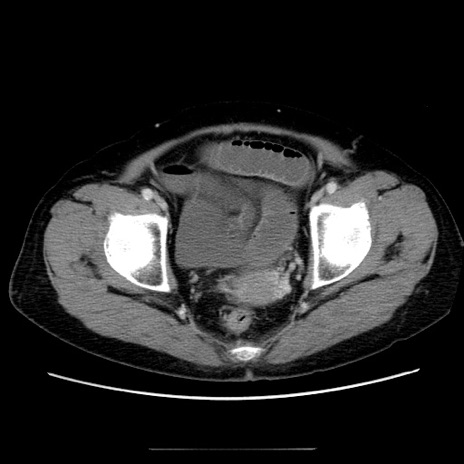

症例5(横断像)

【症例】70歳代女性

【主訴】お腹が張る

【現病歴】1週間くらい前から腹部膨満の自覚あり。昨日夜から増悪したため、本日救急外来受診。

【身体所見】意識清明、BT 36.5℃、BP 165/106mmHg、HR 80bpm、SpO2 98%、腹部:膨満、軟、自発痛・圧痛なし、触診にて不快感あり、腸蠕動音:減弱

【データ】WBC 12600、CRP 1.04